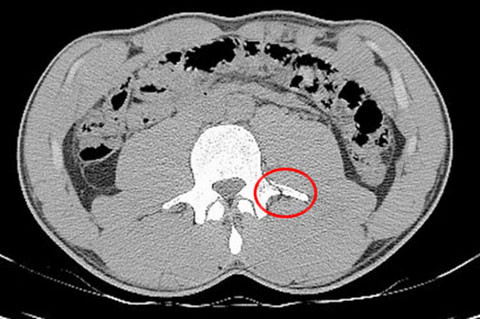

Trong bức ảnh được công bố, chúng ta có thể nhìn thấy rõ một vết rạn ở đốt sống lưng của chân sút 24 tuổi.

Neymar đại nạn không chết, có quý nhân phù trợ ảnh 1Tổn thương nghiêm trọng của Neymar.

Neymar từng lo sợ anh sẽ phải ngồi xe lăn suốt đời nếu như vụ va chạm thấp hơn 2cm. Sau 3 tuần dưỡng thương, Neymar vẫn phải uống thuốc chống viêm và sưng để giảm đau cũng như tăng cường những buổi vật lý trị liệu.